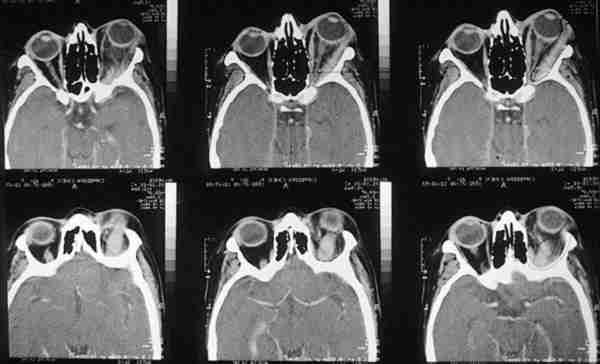

Figura 4. Las leucemias infiltran el globo ocular, nervio óptico y

órbita en varias manifestaciones.